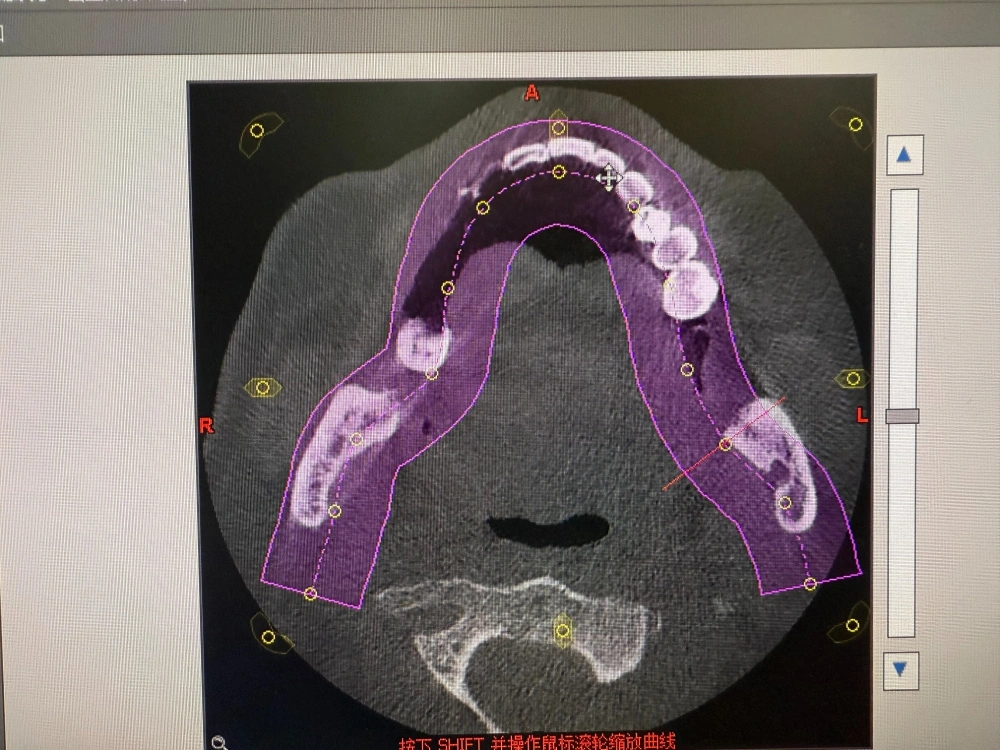

我是当事人的女儿,我父亲今年77岁了,事发前他刚从海南回东北跟我们子女在一起聚聚,他当时有四颗坏掉的牙想尽快根治。7月16日,他看到了哈尔滨市优诺口腔的宣传小广告后一个人去医院咨询,本来想治牙,结果医院建议我父亲把下部的牙全部拔掉后种牙,还说种完牙后吃麻麻香,但现在从片子上来看完全没必要这样做。事发后我们询问了其他口腔医院的医生,所有的医生都说拔牙要评估病人的身体,以我爸高血压、糖尿病、冠心病还有5个心脏支架这种情况,他们可能连拔牙都不会,更不用说一次性拔12颗,甚至还种了6颗,这个破坏是非常大的,正常人可能都受不了,全国都没有这样的案例。

最大的问题是主刀医生,最开始说是由副院长给我父亲进行手术,但实际上并不是他,是一个助理医师给做的。手术全程一个半小时,副院长只在手术室里待了9分钟,9分钟内他把牙钉种在了牙床上,就干了这么一件事,后续带帽、缝合等系列操作全是助理医师独立完成。 种牙是要有资格的,由一名不具备独立操作资格的助理医师实施高风险的手术,属于“非法行医”,整个手术他们存在太多问题了。